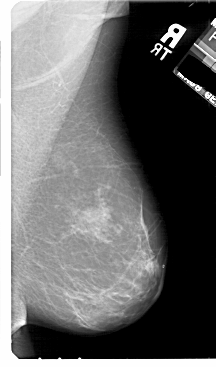

A_1811_1.RIGHT_CC

RIGHT_MLO LINES 5491 PIXELS_PER_LINE 3226 BITS_PER_PIXEL 12 RESOLUTION 43.5 NON_OVERLAY